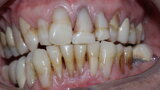

Figure 1 Close up smile before treatment

Figure 2 Full face before treatment